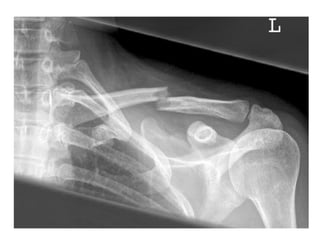

FRACTURAS DE LA CLAVICULA Las Fracturas de la clavícula son frecuentes, en el adulto por traumatismos aplicados en el hombro y en el recién nacido por tracciones efectuadas durante el parto.

FRACTURAS DE LA CLAVICULA Las relaciones que posee la clavícula con los vasos subclavios y nervios braquiales en su trayecto desde la base del cuello hacia la axila motivan que exista un  riesgo potencial de lesión vascular o nerviosa asociado a las fracturas claviculares.

FRACTURAS DE LACLAVICULA Las Fracturas de la clavícula son frecuentes, en el adulto por traumatismos aplicados en el hombro y en el recién nacido por tracciones efectuadas durante el parto.

FRACTURAS DE LACLAVICULA Las relaciones que posee la clavícula con los vasos subclavios y nervios braquiales en su trayecto desde la base del cuello hacia la axila motivan que exista un riesgo potencial de lesión vascular o nerviosa asociado a las fracturas claviculares.